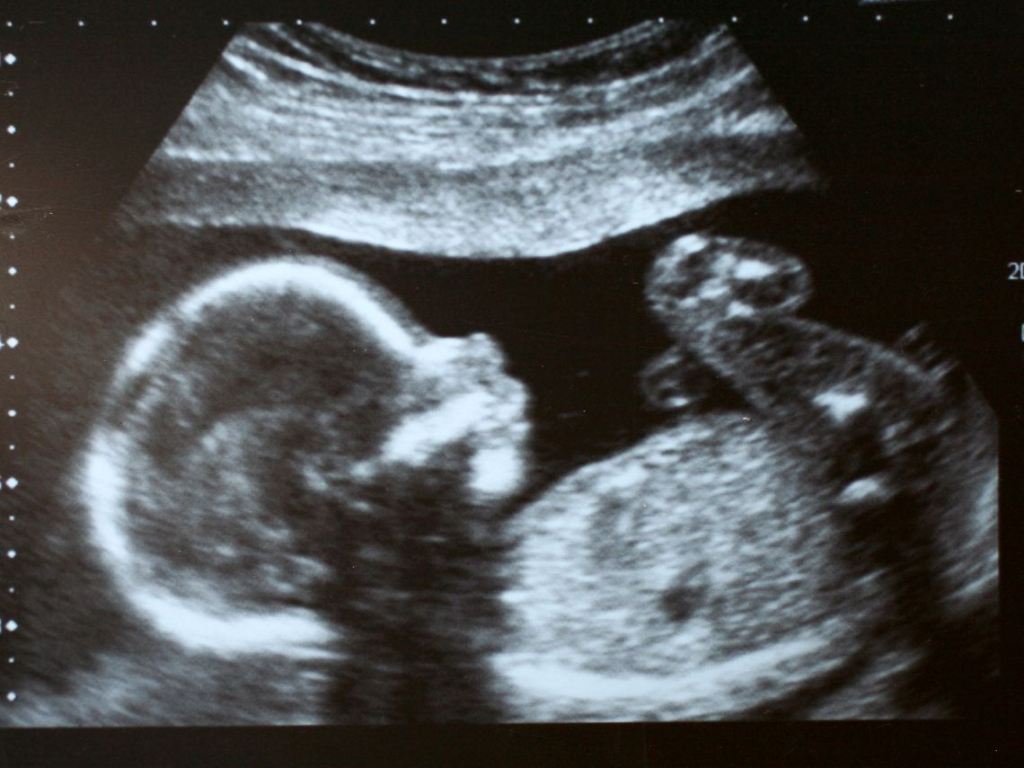

Aunque la confirmación únicamente puede provenir de una ecografía. La ecografía del tercer trimestre, por ejemplo, está especialmente destinada a realizar dicho cribado, dado que el especialista compara el diámetro y el perímetro de la cabeza, pero también la circunferencia de la cintura y la longitud del fémur, con los valores registrados durante la ecografía del segundo trimestre.

Con estos datos, el médico establece una curva de crecimiento. Por lo que, en caso de que se observe una ruptura clara de esta curva, es posible la confirmación de un retraso del crecimiento en el útero.